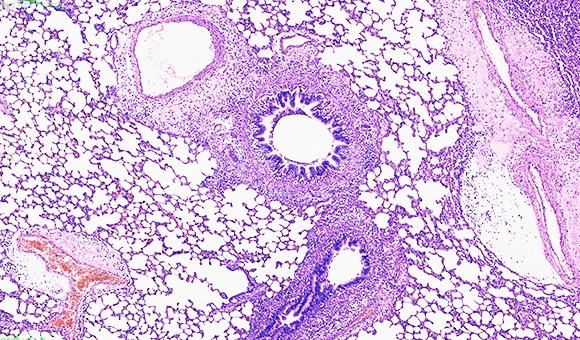

病理分析是探讨器官、组织或细胞所发生的疾病过程,探讨病变产生的原因、发病机理、病变的发生发展过程,最后做出病理诊断。染色针对不同的

病理分析是探讨器官、组织或细胞所发生的疾病过程,探讨病变产生的原因、发病机理、病变的发生发展过程,最后做出病理诊断。染色针对不同的组织情况,通过观察空白组及实验组不同的染色结果来确认病变情况,也可以通过软件来计算病变组织(染色部位)的面积比例。

1 HE病理分析 HE染色病理描述分析